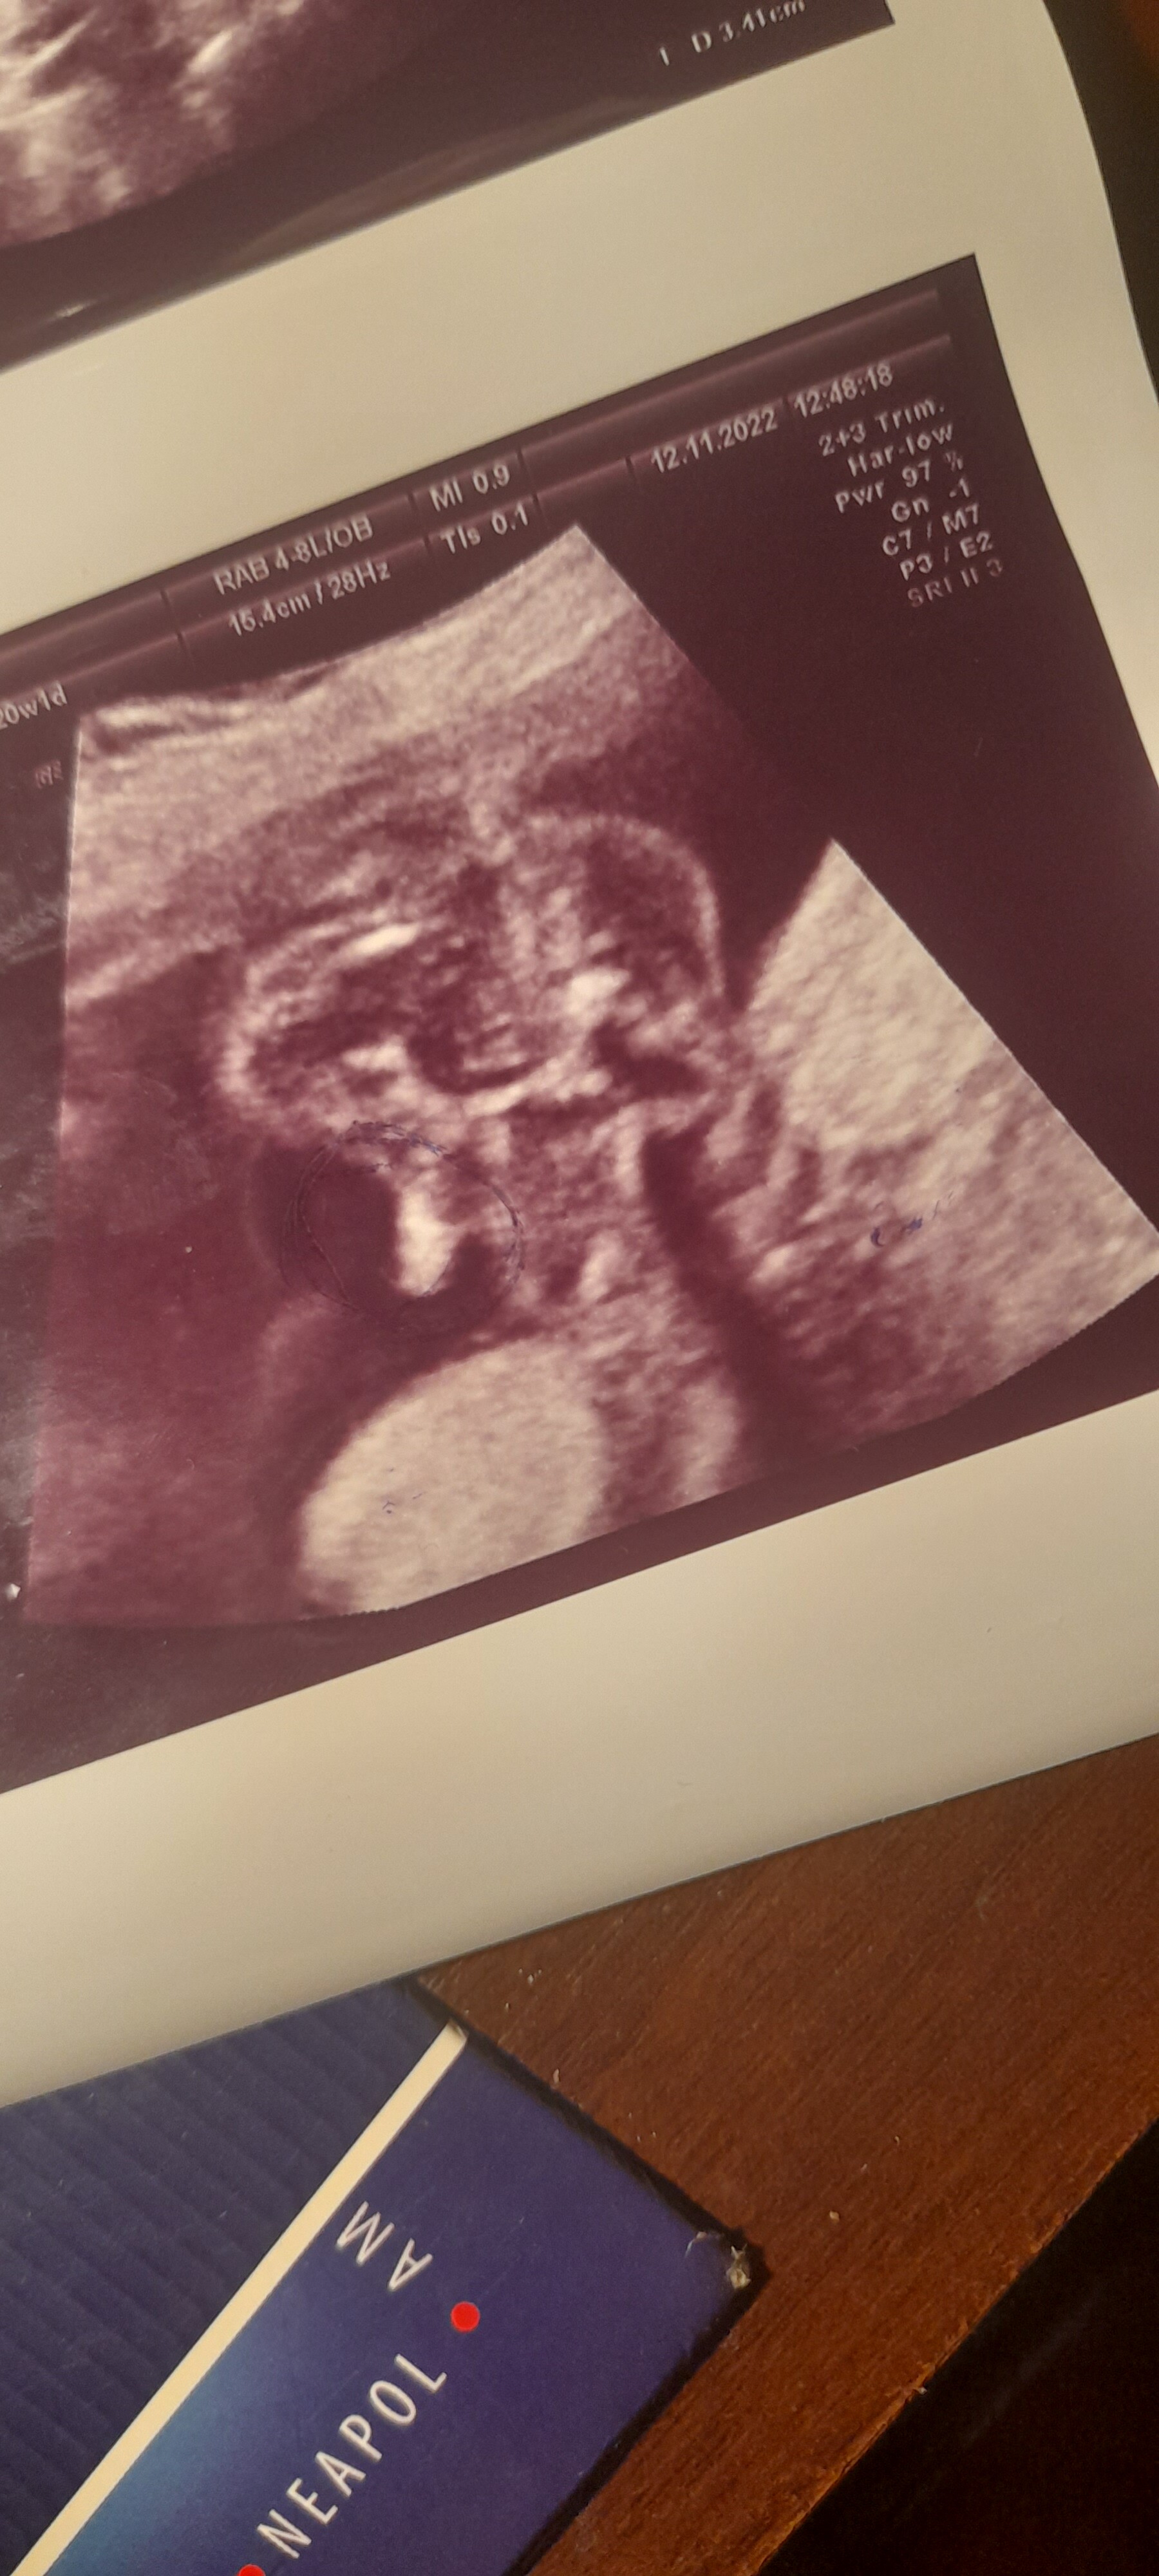

Hej czy można prosić o pomoc. Czy na przedstawionym usg jest pokazane, że jest chłopiec lekarz mówi że jest to siusiak

Wydaje mi się, że to siusiak jednak ;) Wygląda identycznie jak na usg u moich chłopców;)

u nas dwa razy siusiak tez tak wyglądał 🤣

Skoro lekarz powiedział Ci ze to chłopczyk i widać siusiaka to nic tylko mu zaufać i uwierzyć. Gratulacje

Od początku miałam przeczucie, że to dziewczynka. Teraz jest 20 t.c. Bardzo cieszę się na chłopca ale nie potrafię odczytać tego usg. Jest siurek i co dalej? Jakieś dziwne to zdjęcie

Ja bym też się zgodziła z lekarzem, że w brzuszku jest chłopczyk, u dziewczynki to trochę jak taki hot dog wygląda :p